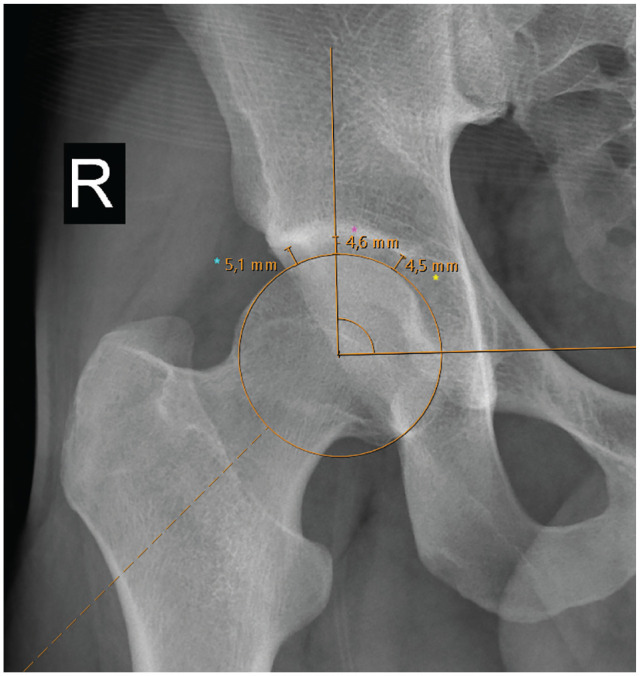

Methods: Patients who had primary hip arthroscopy for FAI between February 5, 2013, and June 1, 2022, with a minimum 2-year follow-up, were included and categorized into 2 age groups (≥35 years and <35 years). Radiographic measurements of JSW on plain anteroposterior pelvic radiographs were used to calculate L/M and C/M ratios. Patient-reported outcomes included the modified Harris Hip Score (mHHS) and visual analog scale for pain. Statistical analysis included chi-square, Mann-Whitney U, and Wilcoxon tests to compare categorical and continuous variables. The receiver operating characteristic (ROC) curve and area under the curve (AUC) assessed threshold values for L/M and C/M ratios predicting the Patient Acceptable Symptom State (PASS) for mHHS at 2 years.

Results: A total of 110 patients (114 hips) were identified, comprising 56 hips from the older group (age ≥35 years) and 58 hips from the younger group (age <35 years). The ROC curve for preoperative C/M effectively distinguished between patients who achieved and did not achieve a second-year PASS value, with an AUC of 0.70 in older patients. Older patients, compared with younger, demonstrated lower postoperative mHHS (89 ± 10 vs 94 ± 8; P = .01) but similar rates of PASS achievement (75% vs 88%; P = .07). The C/M ratio was a significant predictor of functional outcomes in patients aged ≥35. Patients with a preoperative C/M ratio ≥1.08 achieved significantly better outcomes. No significant predictive value was found for L/M ratios in older patients or for L/M and C/M ratios in younger patients.